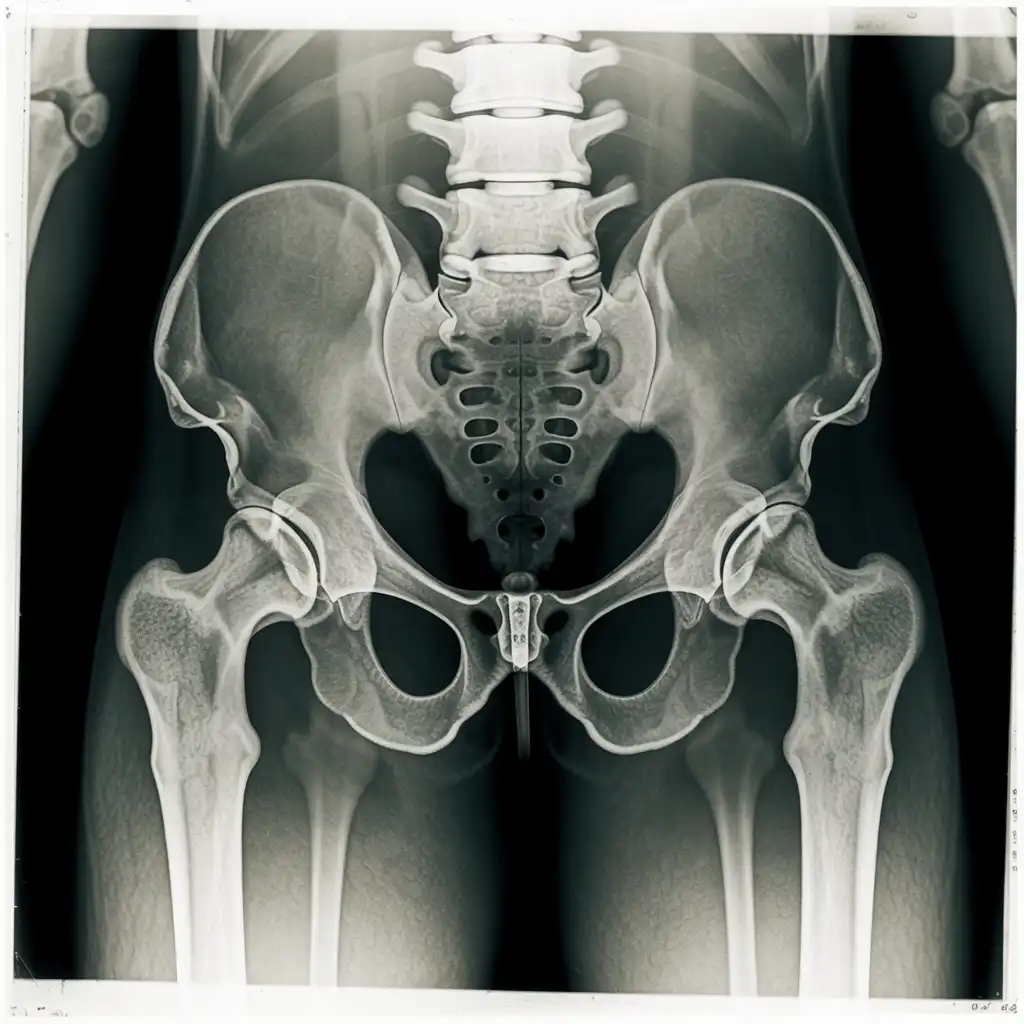

Una lastra a domicilio è una radiografia eseguita direttamente a casa del paziente, grazie all’intervento di un tecnico sanitario qualificato dotato di apparecchiatura digitale portatile.

L’esame viene effettuato sul posto, senza necessità di spostare la persona dal letto o dalla poltrona, e garantisce una qualità diagnostica paragonabile a quella di un reparto ospedaliero.

Una volta acquisite, le immagini vengono trasmesse al medico radiologo, che le analizza e redige il referto in tempi brevi.

Ricevi tutto comodamente in formato digitale: un servizio pratico, sicuro e pensato per chi ha difficoltà negli spostamenti o necessita di un percorso sanitario più semplice e immediato.